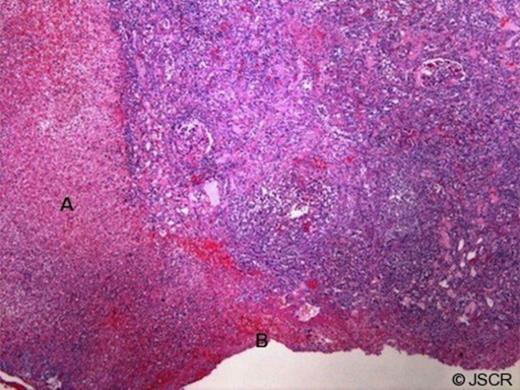

Pathologic examination of the removed kidney demonstrated active infection with bacteria and microabscess (Figure 3). In addition, the granulomatous and necrotising inflammation seemed to coalesce in a fistulous tract toward the renal capsular surface with a surrounding haematoma (Figure 4). Delayed review of the slides following the discovery of his HIV status demonstrated classic focal segmental glomerulosclerosis.

Cortex with necrosis, hemorrhage and fistulous tract (A) associated with capsular hematoma (B) (10x magnification)